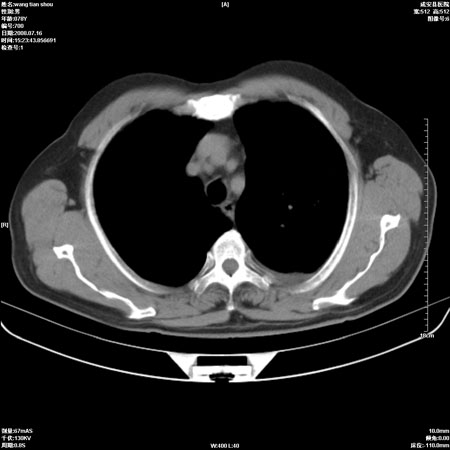

以下是引用qingjing在2008-7-16 19:55:00的发言:[br]1、左上肺不张并堵塞性炎症,建议支气管镜详查;[br]2、左侧胸腔少量积液。

以下是引用wzr在2008-7-16 20:26:00的发言:[br]左肺肺不张伴阻塞性肺炎!另:左侧胸腔少量积液。建议纤支镜检查!